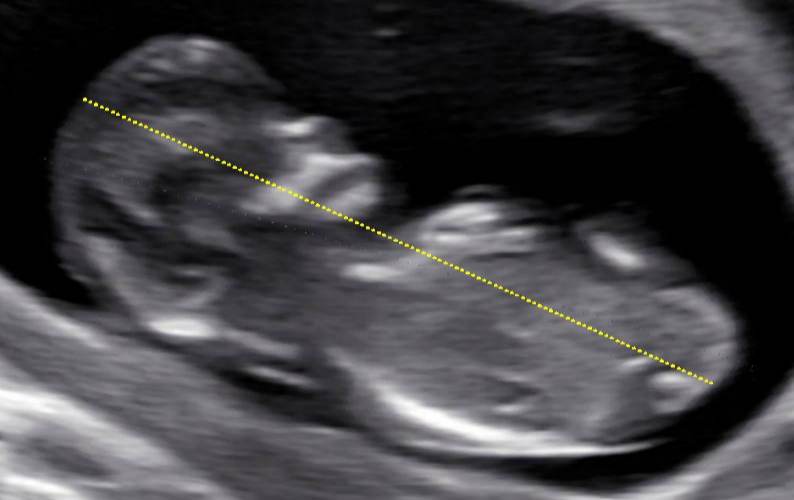

measure the crown rump length (CRL) the image of the fetus or

embryo is obtained in a true midsagittal plane .

The maximum length from cranium (top of the head) to caudal rump (bottom) is measured as a straight line. When possible , the mean of three discrete CRL measurements should be used for estimating the due date.